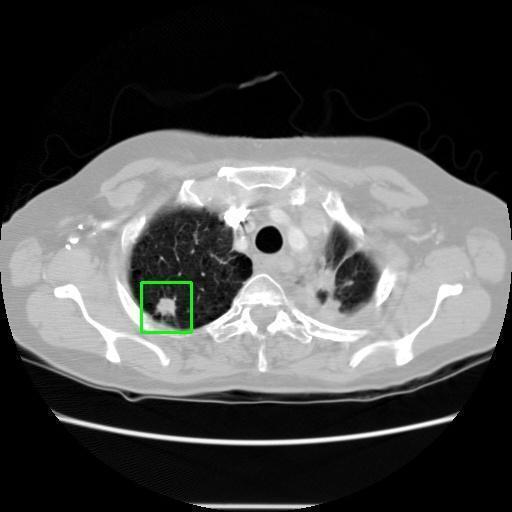

We developed an AI-based system using deep learning models for analyzing lung CT scans to detect and classify pulmonary nodules. We chose the YOLOv11 architecture for its enhanced object detection capability and adapted it specifically for medical imaging, incorporating pixel-level precision and severity classification.

Classification into three severity levels with colored bounding boxes.

Designed a severity classification system that categorizes nodules into null, moderate, and severe using colored bounding boxes, assisting in rapid clinical decision-making.